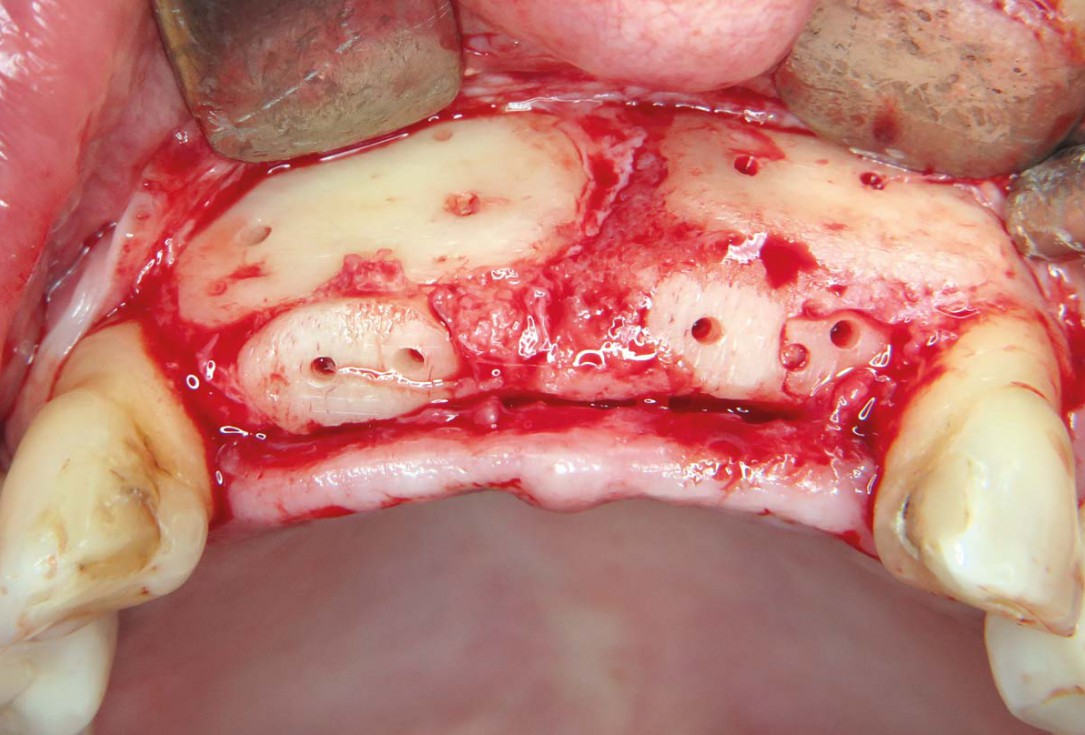

05 / 22 - Fixation of two allogenic cortical plates at the buccal wall

Three-dimensional augmentation with maxgraft® cortico - M.Sc. E. Kapogianni

06 / 22 - Crestal fixation of two allogenic cortical plates for container creation and contouring with cancellous allogenic chips